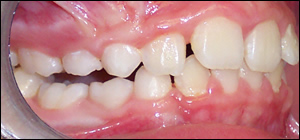

Fig 3: Upon complettion of Twin Block therapy, a Class I molar and skeletal relationship was established. The deep bite was reduced. The spaces between the upper and lower posterior teeth will allow for eruption of the permanent bicuspids.